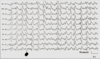

What disease process is this associated with?

What are potential treatment options?

Lennox Gastaut:

Interictal slow spike and wave

- multiple seizure types

- MR

- interictal EEG showing spike & wave

•Possible Rx: felbamate, rufinamide

Appears between ages 1 and 10, sometimes de novo, sometimes after infantile spasms.

• Triad of

(1) multiple seizure types refractory to AEDs,

(2) mental retardation (most), and

(3) slow spike-and-wave (1.5-2.5 HZ) activity on EEG.

Lennox-Gastaut Syndrome